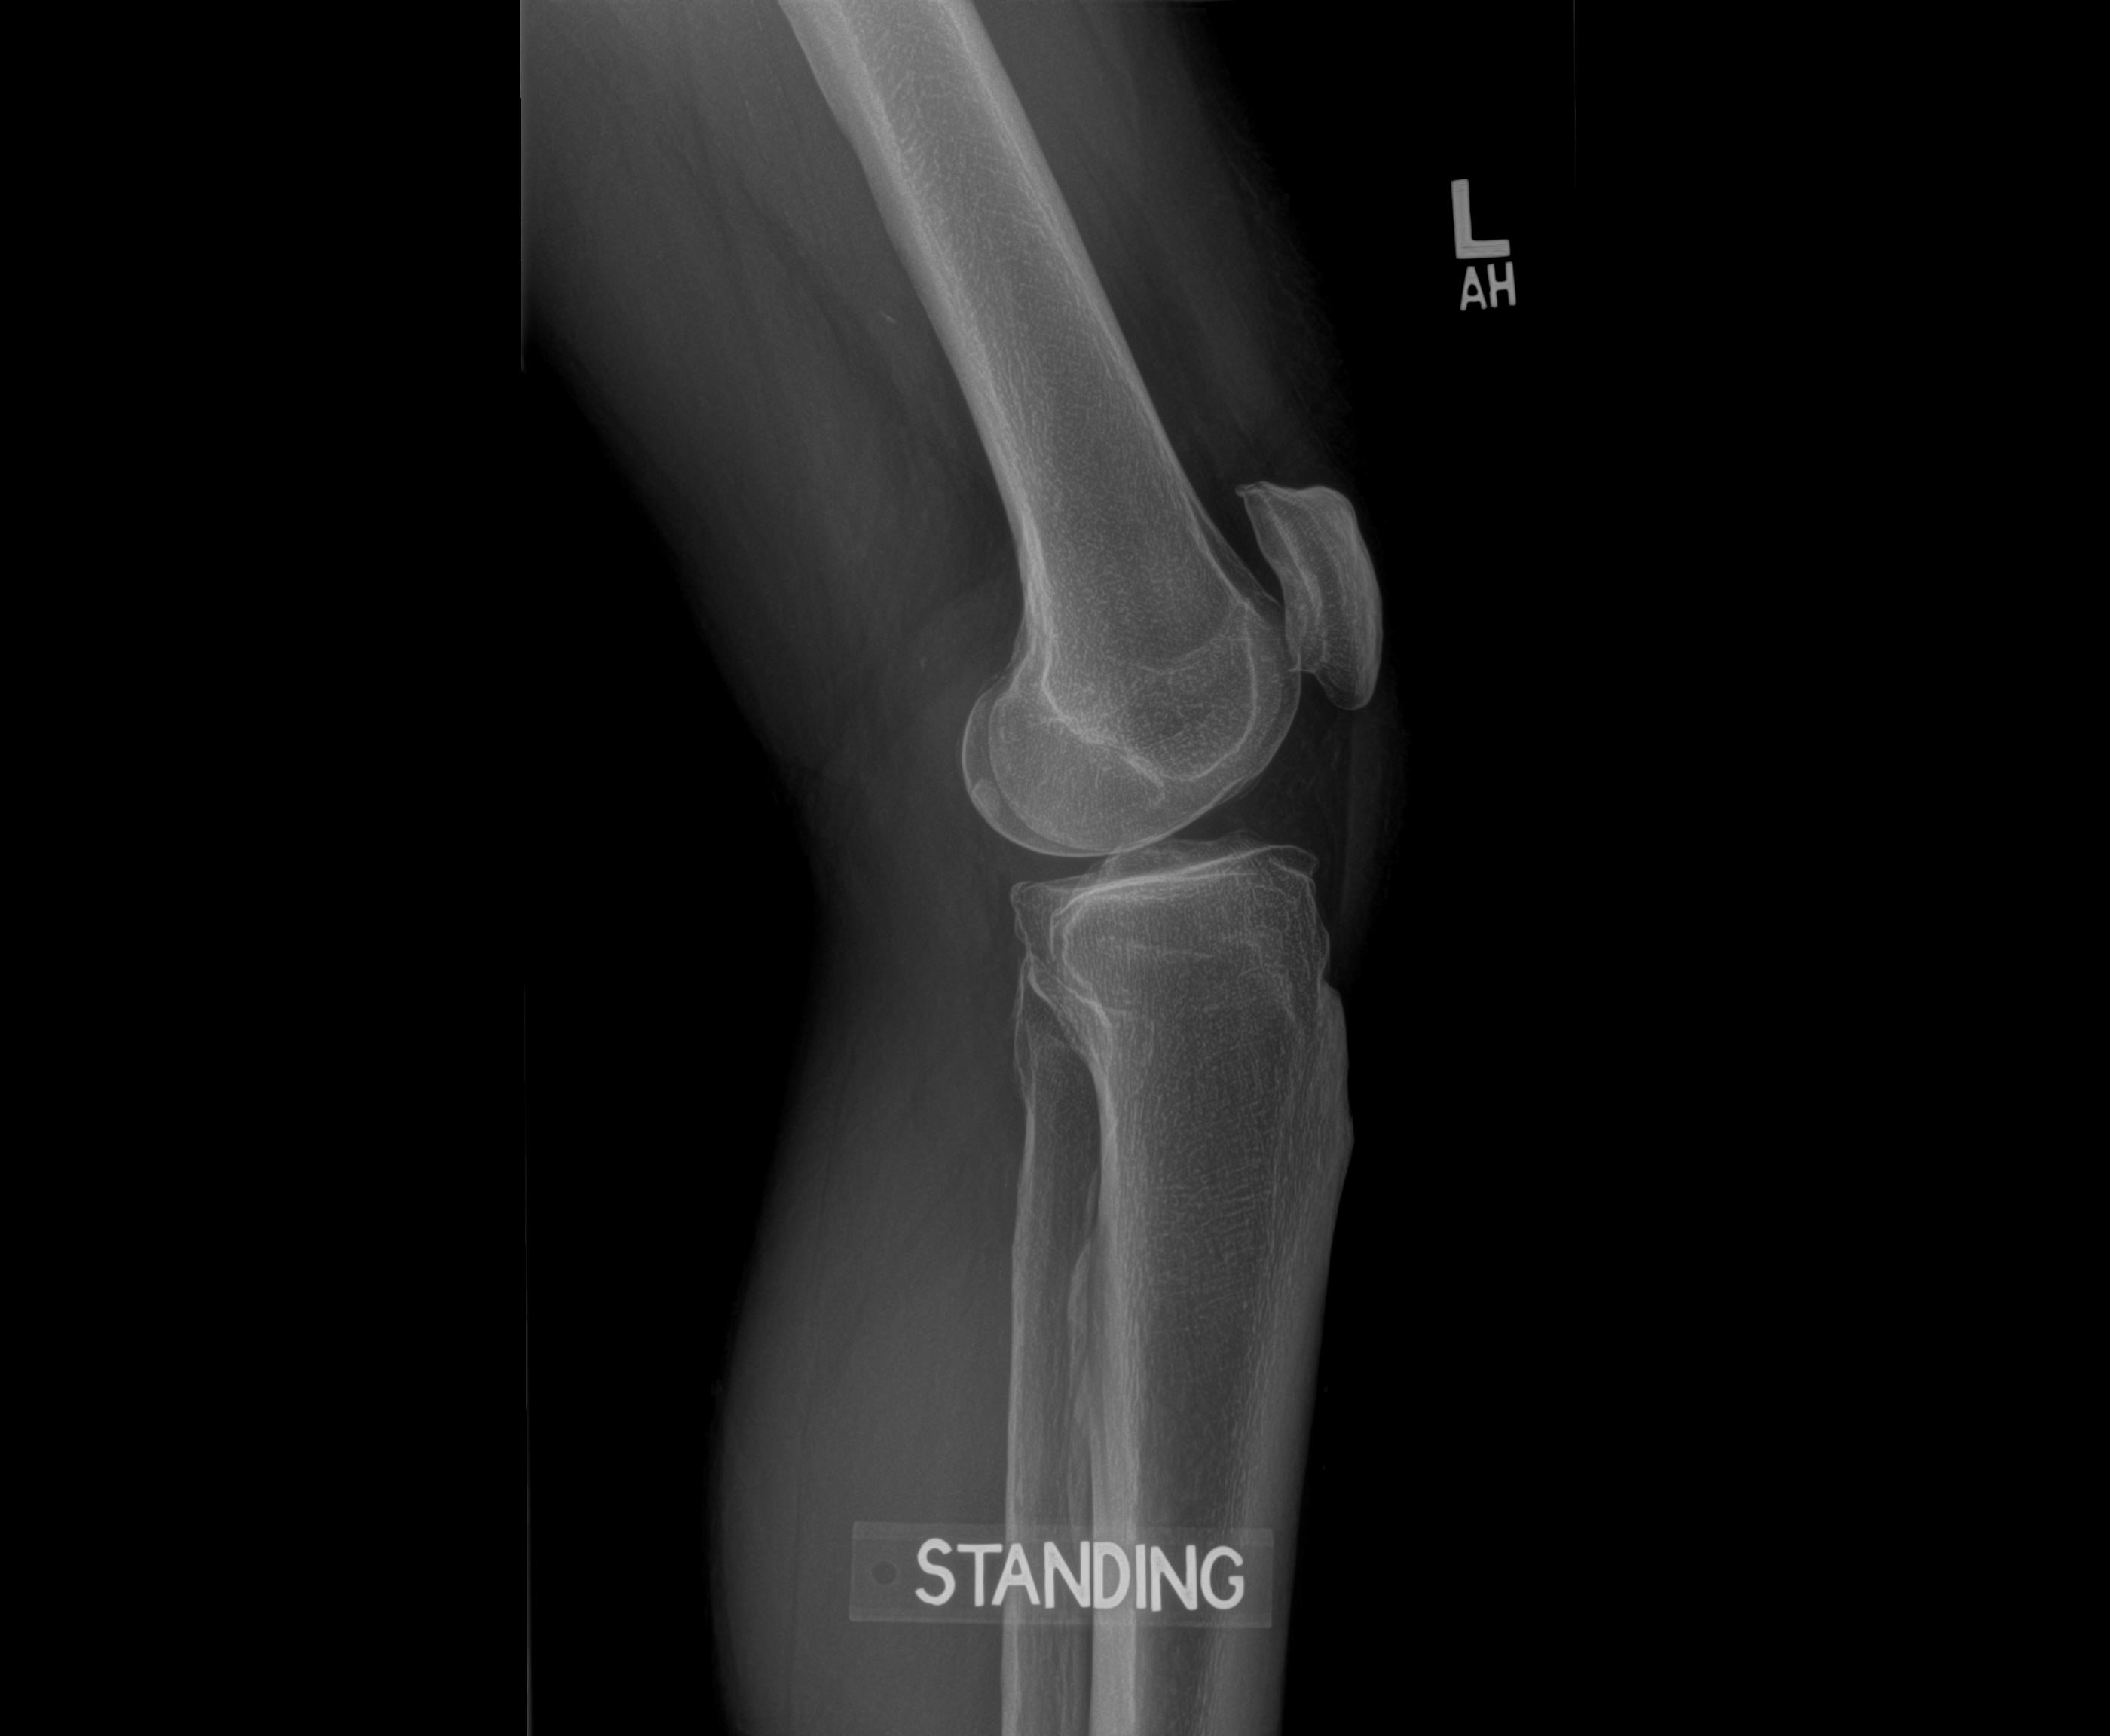

Before – Left Knee

Before – the left knee